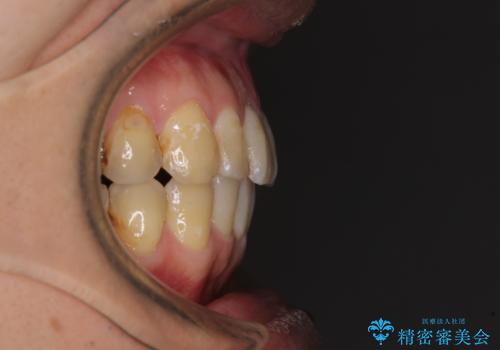

前歯のデコボコと下顎の八重歯 インビザラインによる矯正治療

- 前歯のデコボコや八重歯を気にして来院された患者様です。

インビザラインを用いて、歯列を整えることとしました。